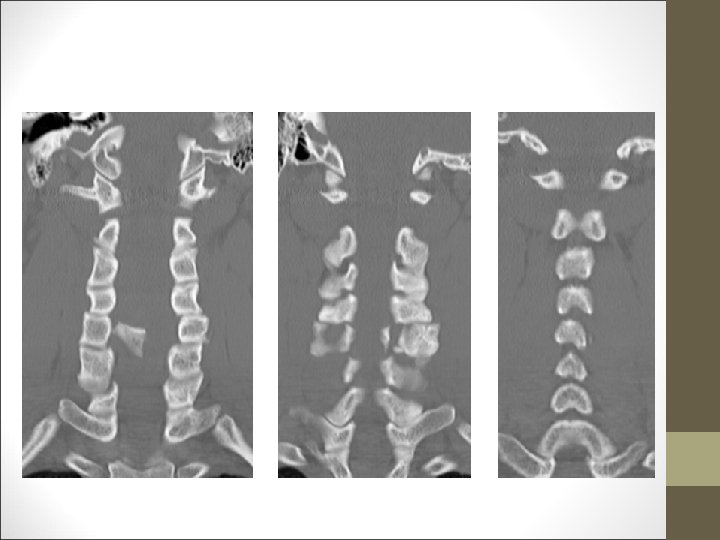

FACULTAD DE MEDICINA DEPARTAMENTO DE CIRUGÍA NEUROCIRUGÍA ¿Qué harías? TAC Cervical

TC Desplazamientos de fragmentos óseos ¿Algo mas? FACULTAD DE MEDICINA DEPARTAMENTO DE CIRUGÍA NEUROCIRUGÍA RM Desplazamientos discales y lesiones ligamentosa